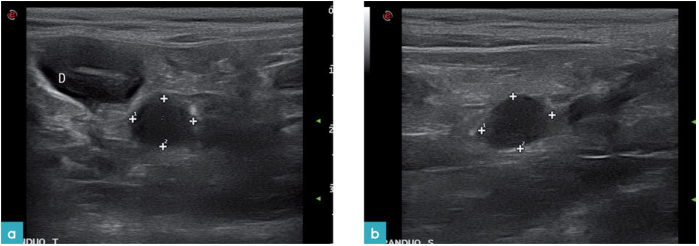

恶性病变的淋巴结通常是均质的低回声圆形的结构(图14)。但是如果淋巴结发生了出血,坏死或者钙化,则会变得回声不均匀(图15)。在犬的恶性肿瘤时会发现回声不均匀的淋巴结。与猫恶性肿瘤的相关性目前没有被证实。

淋巴结病与反应性淋巴结病,炎症和肿瘤有关(图16)。超声上不能完全区分正常淋巴结,反应性淋巴结,以及恶性转移性淋巴结,他们之间有相似之处(图17)。形态较大,回声混杂的淋巴结可能为良性或恶性肿瘤浸润的淋巴结,也可与脓性肉芽肿(图18)或肿瘤(图19)相关。应该细针抽吸淋巴结做细胞学诊断。